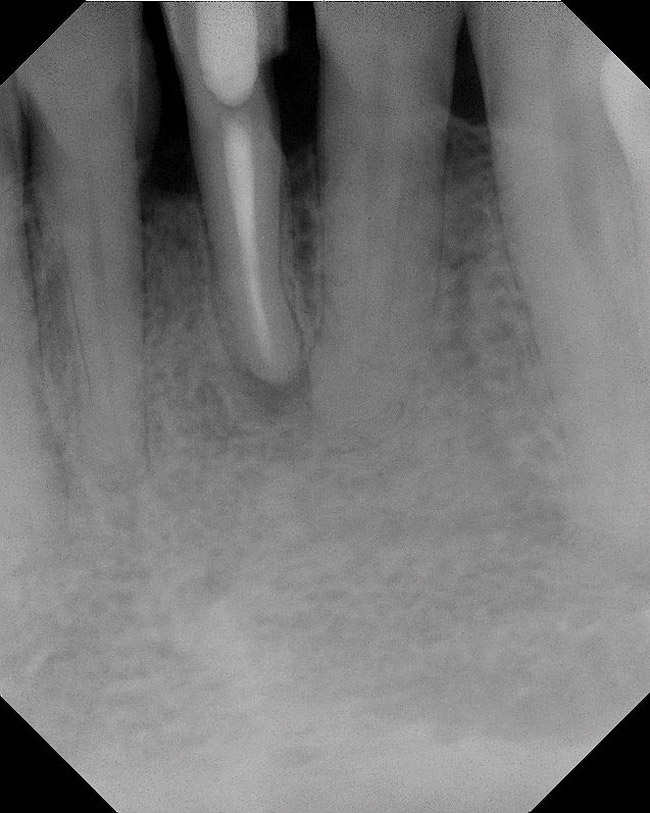

As mentioned, all risk factors associated with both root canal and implant therapy must be carefully considered. Comprehensive clinical and radiographic assessments are necessary to evaluate the patient's risk factors associated with his or her particular case (Figure 1, Figure 2 and Figure 3). The primary risk factors for implants can include smoking, bone quality, and systemic health. For endodontic therapy the primary risk factors are related to the anatomic root complexity, failed root canal treatment with significant technical defects manifested as iatrogenic events, less-than-optimal periodontal status of the tooth (due to a subsequent risk of vertical fracture), and a clinician's lack of experience with regard to the case's complexity. A strong correlation exists between failed root canal treatment and a lack of coronal seal after treatment. This is highly relevant in treatment planning. Often, endodontically treated teeth fail not because they were treated inappropriately and need extraction, but rather, because they have been left unsealed and assaulted by bacteria after the endodontic therapy, causing subsequent long-term clinical failure (Figure 4 and Figure 5).

While not elaborated on here, it is noteworthy that there are a number of additional treatments for resorption that have been suggested in the literature, including calcitonin,27 Emdogain,24,28 and Alendronate (third-generation bisphosphonate in treating EIRR)29 (Figure 6, Figure 7, Figure 8, Figure 9, Figure 10, Figure 11, Figure 12, Figure 13, Figure 14 and Figure 15).